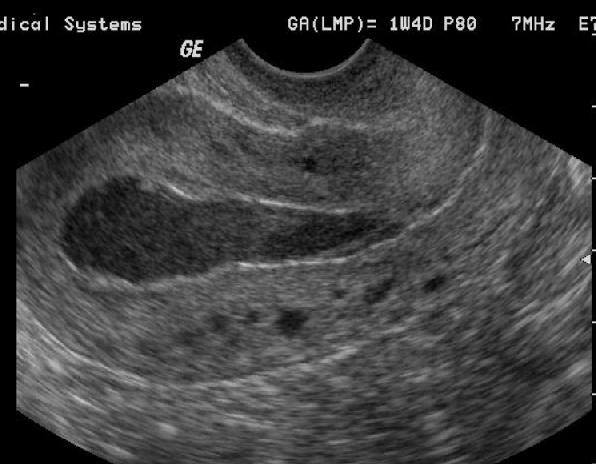

Adenomyosis

Glándulas de tejido endometrial que crecen en el miometrio

Visto en mujeres luego de los 40 años

Síntomas: dismenorrea y

sangrado anormal

Se ha asociado con alza en estrógeno

Por sonografía: Útero Grande e hipoecoico

especialmente durante

la menstruación.

Se diagnostica con facilidad con MRI